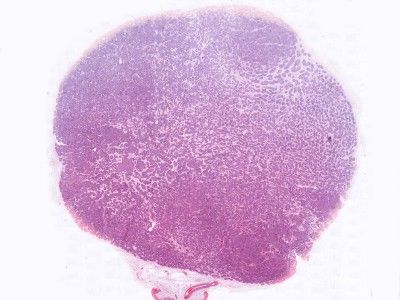

PA:De tumor ligt

los van de epidermis en is opgebouwd uit talloze polygonale nesten van

tumorcellen die als een puzzel in elkaar passen ('jigsawlike pattern').

Typisch is ook dat de velden omringd zijn door een dikke hyaliene membraan.

Deze membraan bestaat vooral uit type IV collageen. In de velden kunnen 2

celtypen worden onderscheiden: een rand van kleinere basofiele cellen en een

centrum van grote bleke cellen. Ook buisvormige structuren en lumina kunnen

worden gezien. In tegenstelling tot spiradenoma ontbreekt een lymfocytair

infiltraat. Wel worden dendritische cellen gezien, waarschijnlijk Langerhans

cellen (CD1a-positief). Immunohistochemische kleuringen tonen

myoepitheliale, apocriene, eccriene, ductale, and secretoire differentiatie

aan. Zie ook de

ingescande PA-coupe van de

afdeling pathologie van de University of

Toronto.

![Histologie cylindroma (click on photo to enlarge) [source: Kevin Kwee / Afdeling Pathologie MUMC] Histologie cylindroma](../../../pacoupes/thumbnails/cylindroom.jpg) |

![Histologie cylindroma (click on photo to enlarge) [source: Kevin Kwee / Afdeling Pathologie MUMC] Histologie cylindroma](../../../pacoupes/thumbnails/cylindroom-eccrien.jpg) |

| ingescande coupe (zoom) |

ingescande coupe (zoom) |